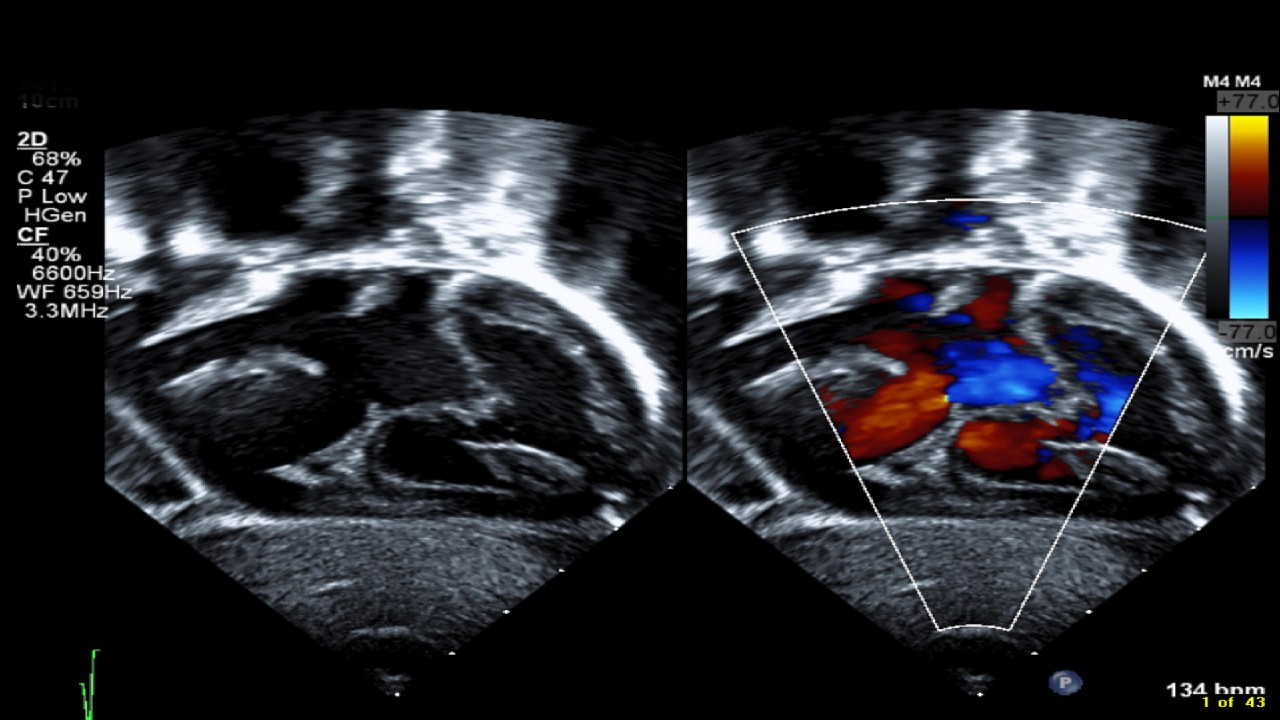

2. Echokardiografija (širdies echoskopija) – pagrindinis tyrimas, leidžiantis matyti defekto vietą, dydį ir kraujo tekėjimo kryptį.